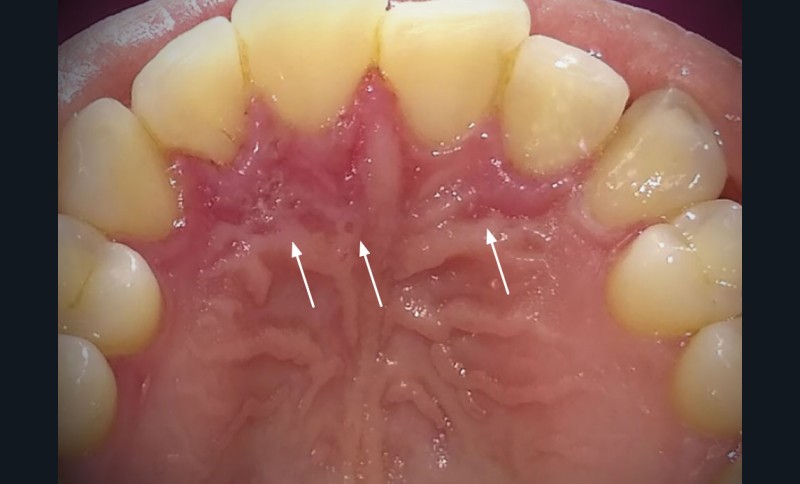

Présence de zones d’érosions post-vésiculeuses regroupées en « bouquet » en palatin des 12, 11 et 22 (fig. 1a) et au niveau de la gencive marginale de la 23 (fig. 1b). Les muqueuses affectées étaient enflammées et sensibles au toucher. Pas d’adénopathie cervico-faciale palpable et pas d’atteinte extra-orale.